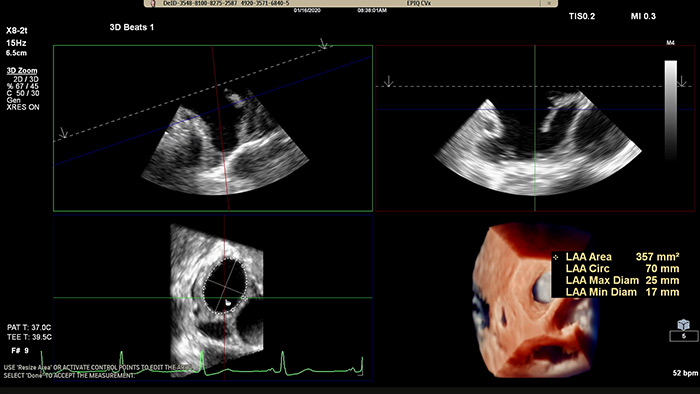

Быстрое измерение отверстия в ушке левого предсердия с использованием традиционных алгоритмов визуализации или алгоритмов визуализации TrueVue Glass с приложением 3D Auto LAA